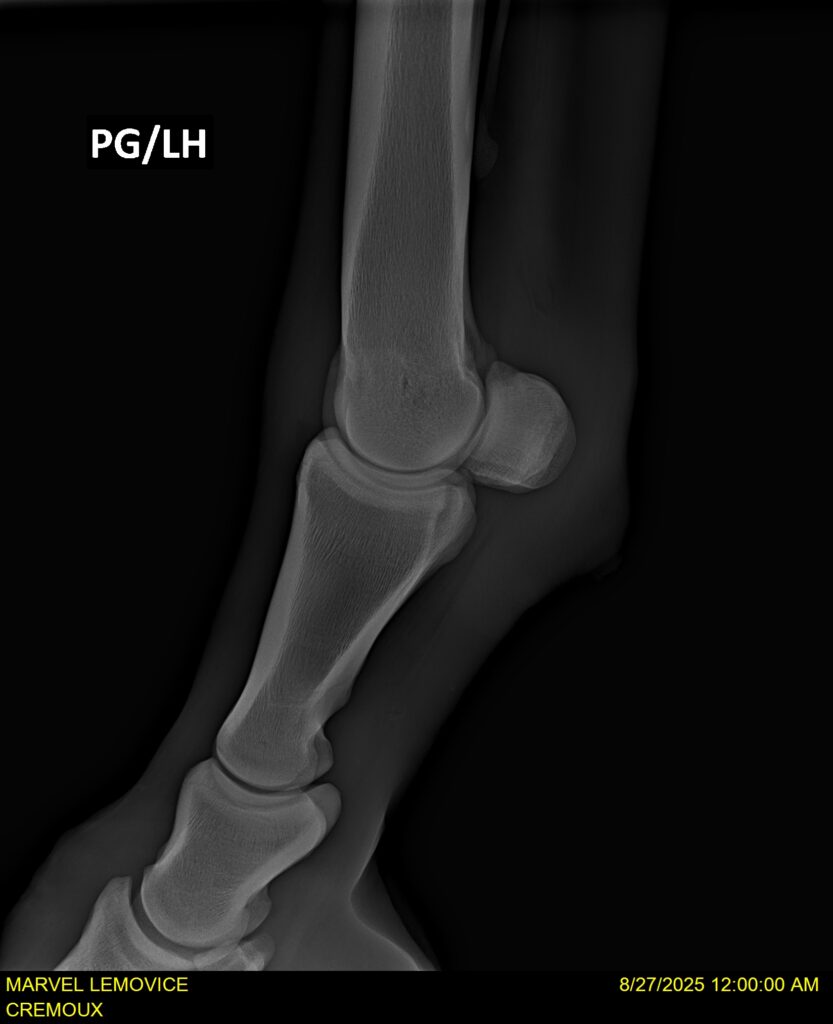

MARVEL LEMOVICE, hongre, Selle Français prend 4 ans en 2026. POPSTAR LOZONAIS x ROSIRE sur une excellente souche maternelle de l’élevage PLATIERE. Débourré aux trois allures et mise en route à l’obstacle. Super modèle avec du cadre et de la force, cheval respectueux avec des moyens. Très agréable au quotidien. Transport OK, maréchalerie OK, santé RAS, Bilan 20 clichés radios + clinique OK.

RADIOS ET CLINIQUE